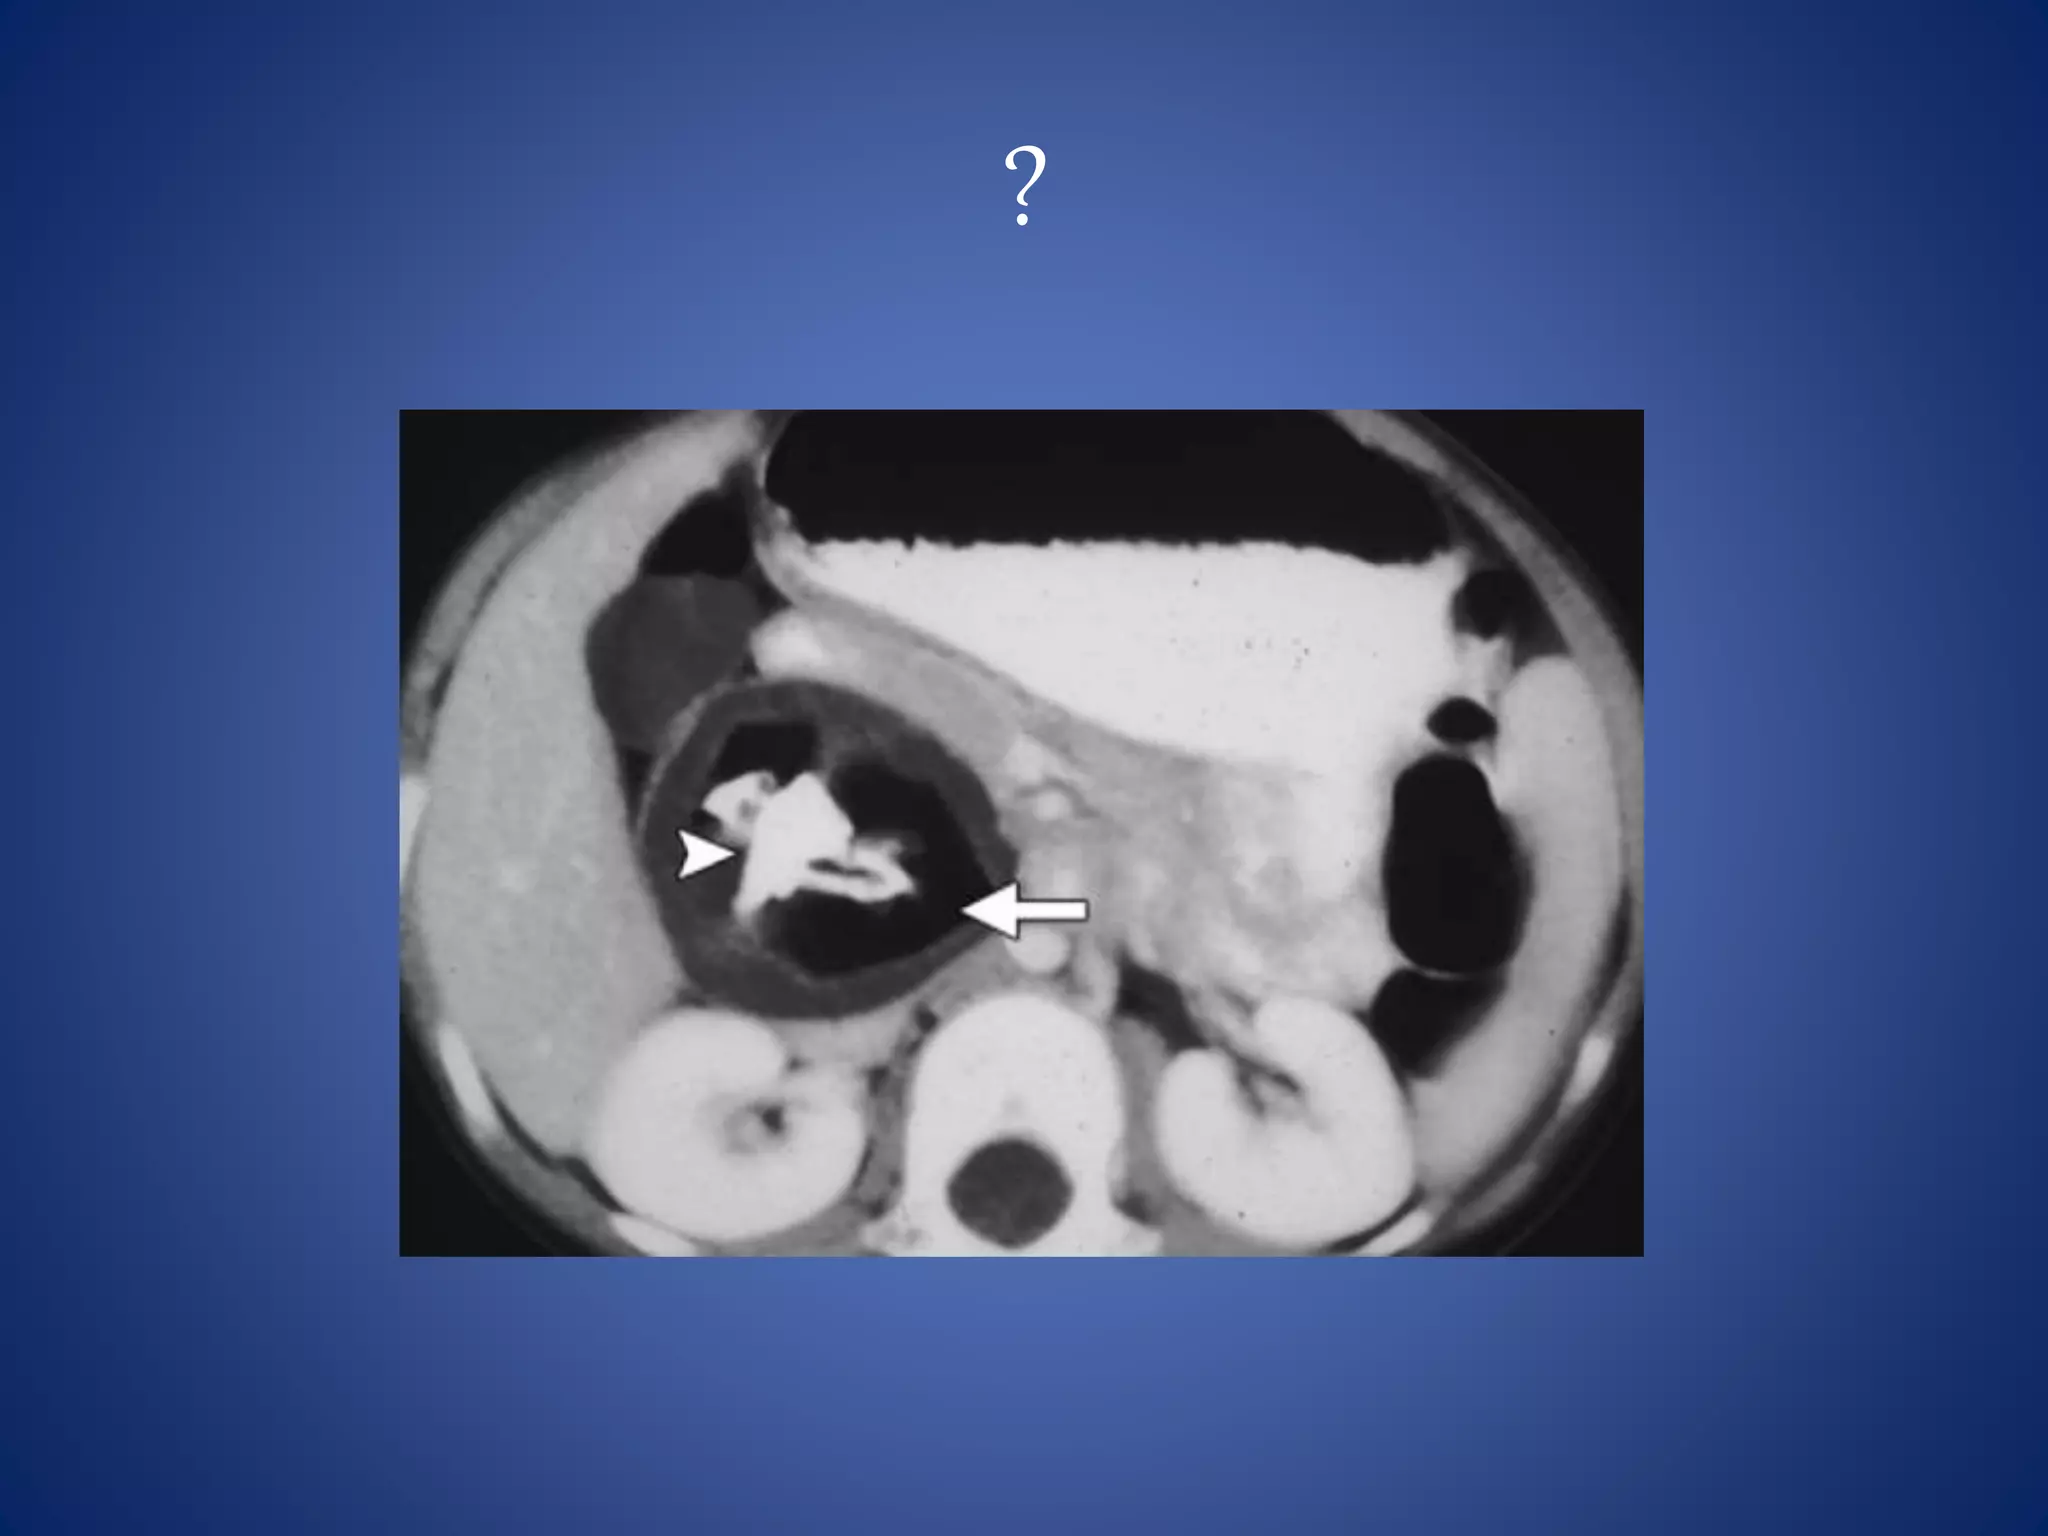

Leiomyosarcoma

Leiomyosarcoma is the second most common (28%) primary

retroperitoneal sarcoma.

It arises from retroperitoneal smooth muscle tissue, blood vessels,

or wolffian duct remnants and can grow to a large size (>10 cm)

before compromising adjacent organs and precipitating clinical

symptoms such as venous thrombosis.

It is more common in women, in the 5th to 6th decades.

Leiomyosarcoma can be predominantly extravascular (62%) or

intravascular (5%) in the retroperitoneum or can have

a combination of extra- and intravascular components (33%).

At CT, small tumors may be homogeneously solid, but large tumors

have extensive areas of necrosis and occasional hemorrhage.

The presence of extensive necrosis in a retroperitoneal mass, with

contiguous involvement of a vessel, is highly suggestive of

leiomyosarcoma.

Approximately 6% of leiomyosarcomas arise from the IVC.

Most of these tumors have a large extravascular component that

makes it difficult to distinguish them from a secondary involvement

of the IVC with an extrinsic tumor.

The most commonly affected location is the segment between the

diaphragm and renal veins.

• #74 Leiomyosarcoma --- The presence of extensive necrosis in a retroperitoneal mass, with contiguous involvement of a vessel, is highly suggestive of leiomyosarcoma 6% of leiomyosarcomas arise from the IVC